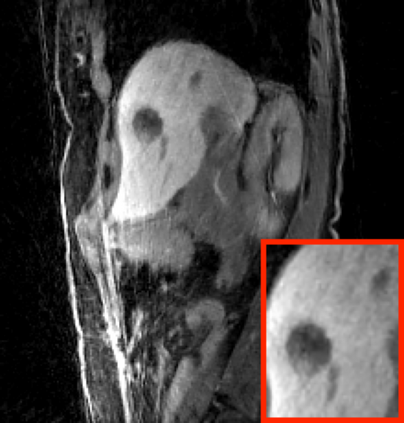

Deep neural networks for medical image reconstruction are traditionally trained using high-quality ground-truth images as training targets. Recent work onNoise2Noise (N2N) has shown the potential of using multiple noisy measurements of the same object as an alternative to having a ground truth. However, existing N2N-based methods cannot exploit information from various motion states, limiting their ability to learn on moving objects. This paper addresses this issue by proposing a novel motion-compensated deep image reconstruction (MoDIR) method that can use information from several unregistered and noisy measurements for training. MoDIR deals with object motion by including a deep registration module jointly trained with the deep reconstruction network without any ground-truth supervision. We validate MoDIR on both simulated and experimentally collected magnetic resonance imaging (MRI) data and show that it significantly improves imaging quality.